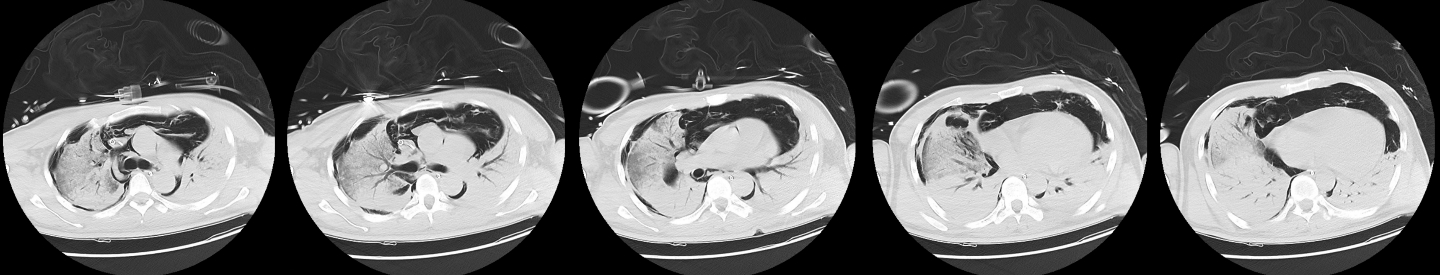

1 病例资料2024-11-15,某工地操作间有值班人员3人,分别为上铺(距地面1.8 m)A某,下铺(距地面0.4 m)B某、C某,事发当天为午休时间,设备出现故障,下午14时维修人员D某进入操作间维修,并将门窗打开,完成维修操作;事发后24 h内4名患者均出现不同程度的恶心、呕吐等消化道症状,起初考虑可能与食物中毒有关,前往当地医院就诊,完善血便常规、胸腹CT等相关检查未见明显异常,在医院给予吸氧补液静卧留观,留观期间4人先后出现不同程度的咽痛、咳嗽、胸闷、憋气等不适,吸氧不能缓解,再次行胸部CT检查示双肺弥漫性改变,间质改变可能,考虑为吸入有毒有害气体,后经采样检测操作间气体残留为全氟-4-甲基-2戊稀[Perfluoro(4-methylpent-2-ene),D1](D1纯度99.92%),导致急性呼吸窘迫综合症(acute respiratory distress syndrome, ARDS)。参照2002年职业性急性有机氟中毒诊断标准[1],A某诊断为急性中度有机氟气体中毒,B某、C某、D某诊断为急性重度有机氟气体中毒(PaO2/FiO2 < 100 mmHg,1 mmHg=0.098 kPa)。立即给予大剂量(120 mg)甲泼尼龙琥珀酸钠治疗,同时补充多种微量元素,加用甲钴胺、硫辛酸,钙剂解毒,后续加用特殊解毒剂乙酰胺治疗。治疗1周后,上铺的A某胸闷、憋气症状较前好转,影像未见明显进展,但患者仍遗留有间断气短症状;其余人员病情持续恶化,出现呼吸衰竭,转入重症医学科,给予气管插管接呼吸机辅助通气,维修人员D某上呼吸机后能基本维持,但不能脱机,继续观察患者病情变化;而下铺患者B某、C某症状不断加重,即使给予呼吸机治疗低氧状态仍未见明显改善,于2024-11-29转入本院进一步治疗。B某、C某入本院时查体:双肺叩诊呈清音,双肺呼吸音粗,可闻及干湿性啰音,具体指标见表 1,图 1、2为肺部影像进展情况。入院给予镇静镇痛、机械通气及抗感染、抗炎、抑酸等治疗,呼吸困难仍持续加重,存在难以纠正的低氧血症及高碳酸血症,表现为ARDS,有体外膜肺氧合(extracorporeal membrane oxygenation, ECMO)治疗指征,参考国内外相关救治经验[2-6],给予患者静脉-静脉ECMO(veno-venous extracorporeal membrane oxygenation, V-V ECMO)治疗,具体参数见表 2。

| 图 1 B某发病第1、3、10天胸部CT |